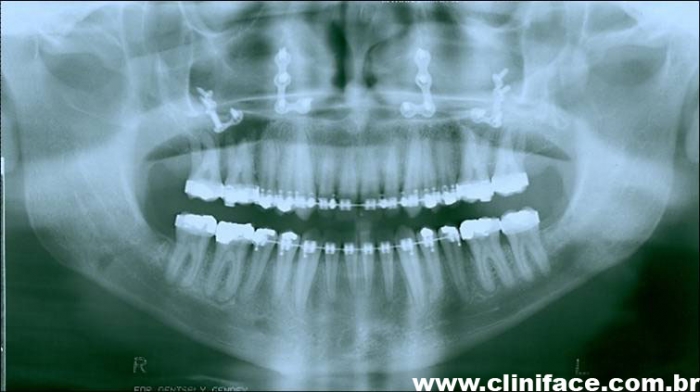

Raio X panorâmico inicial